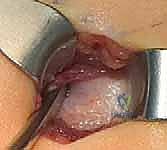

بدلاً من فتح الساق بالكامل، يقوم الدكتور هطيف بعمل ثقوب صغيرة جداً (مليمترات) في الجلد. باستخدام أدوات دقيقة جداً (مثل الإزميل الدقيق أو المثقاب المتخصص)، يتم قطع العظم في أماكن التقوس من الداخل دون إتلاف الأنسجة الرخوة أو العضلات المحيطة. هذا يحافظ على التروية الدموية للعظم (Periosteum)، مما يسرع من التئام العظم بشكل مذهل.

بعد تقويم العظم وجعله مستقيماً كحبات المسبحة على خيط، يتم إدخال السلك الدليلي (Guide Wire). ثم يتم إدخال الجزء الخارجي (الأنثوي) من المسمار التلسكوبي وتثبيته في الجزء العلوي من العظم (Epiphysis).

بعد ذلك، يتم إدخال الجزء الداخلي (الذكري) من المسمار عبر الجزء السفلي من العظم وتثبيته في المشاشة السفلية. هذا التصميم العبقري يضمن حماية العظم بالكامل من الداخل.